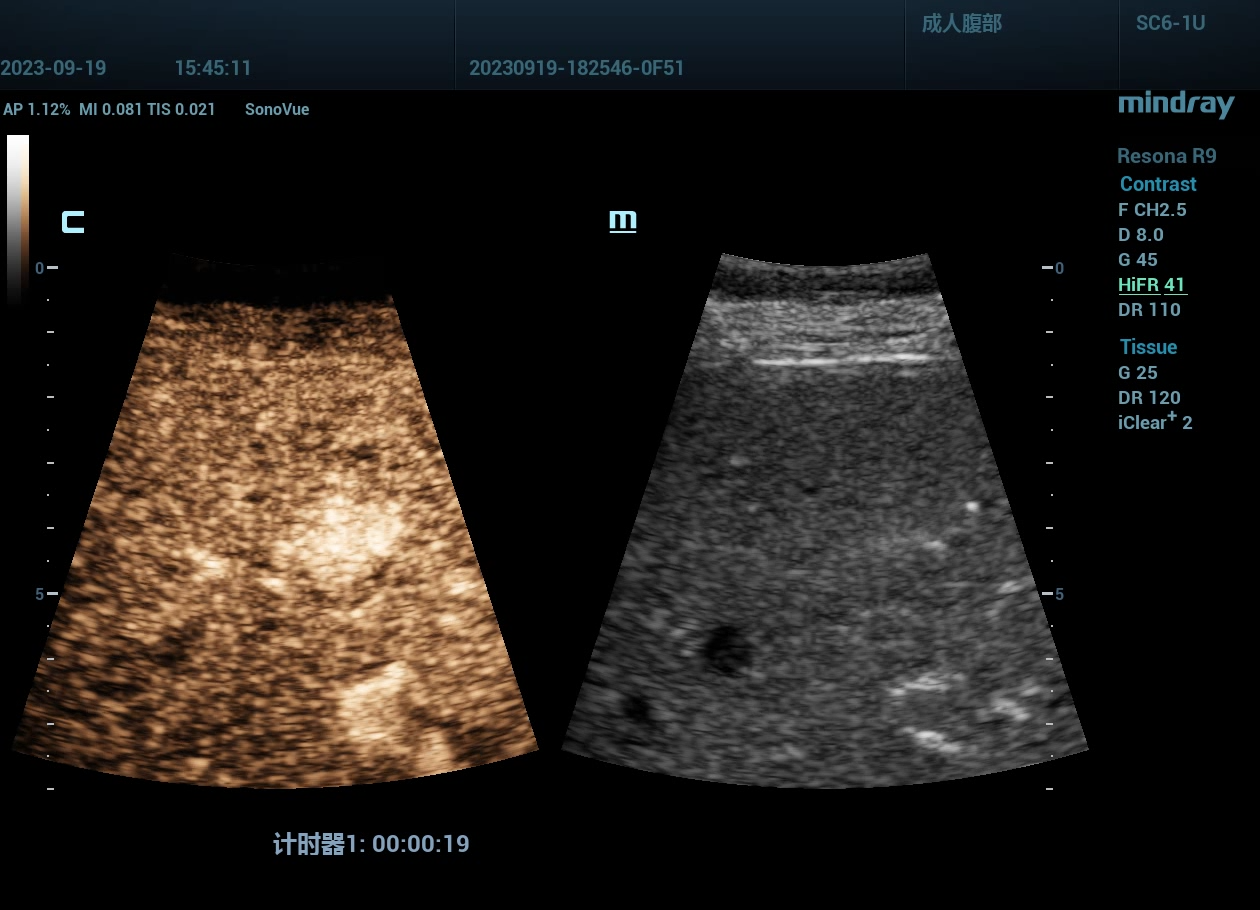

肝脏超声造影病例,FNH,高帧率造影,病例来源广西区人民医院

肝脏超声造影病例,FNH,高帧率造影,病例来源广西区人民医院。